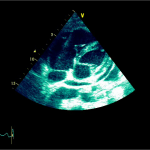

Ecocardiografia transtoracică

- Formaţiune hiperecogenă cu suprafaţa neregulată, care tapetează peretele liber al VD, grosime de 12 mm

- Dispusă de sub planul valvei tricuspide până in apropierea conului de ejecţie al valvei pulmonare

- SIV aplatizat

Ecografia transesofagiană:

Confirmă datele de la ecografia transtoracică